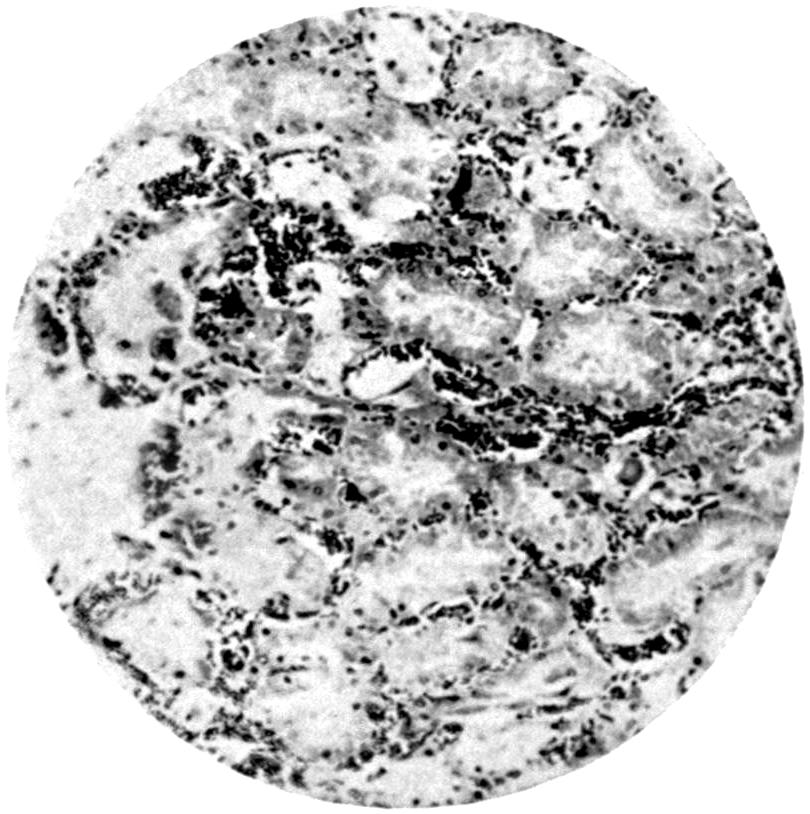

Plate I. 92

Plate II. 93

Plate III. 95

Plate IV. 276